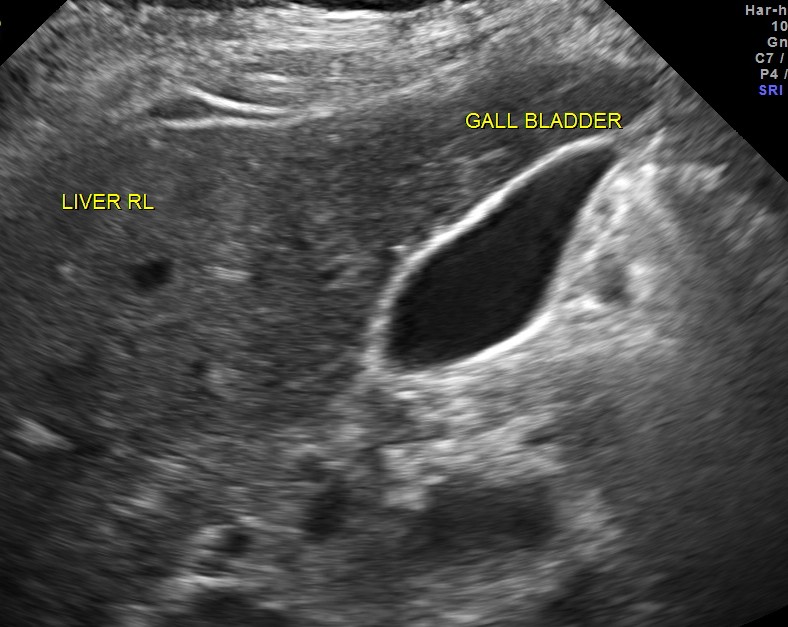

Ultrasound of the liver, gall bladder , pancreas and spleen revealed no abnormality.